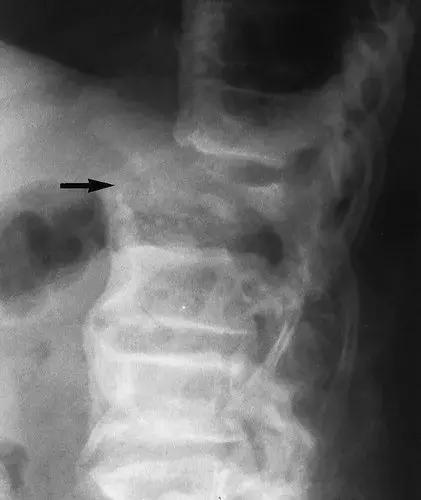

图5: 66岁女性,糖尿病引起的轴性神经性骨关节病。 (a)腰椎的侧位X线片显示T12的破坏(箭头)和后半脱位。 (b)T12椎骨的轴向CT扫描显示椎管内的骨质碎片(实线箭头), 后部附件破裂碎片,表明神经病因。 多个活组织检查样本未能显示感染或肿瘤。